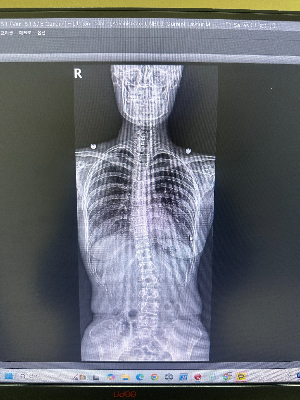

정상적인 사람의 척추를 정면에서 바라보면 완벽한 일직선(I자)을 이루어야 합니다. 하지만 척추측만증 환자의 척추는 정면에서 보았을 때 S자나 C자 형태로 심하게 휘어져 있으며, 심한 경우 척추뼈 자체가 꽈배기처럼 회전하면서 변형됩니다.

의사 선생님은 전척추 엑스레이 사진을 띄워놓고 척추가 가장 많이 휘어진 위쪽 뼈와 아래쪽 뼈를 찾아 선을 그어 각도를 측정합니다. 이를 '코브 각도(Cobb's Angle)'라고 부릅니다.

아까 엄마한테 유난 떤다며 짜증을 내던 그 여중생, 진료실 모니터에 뜬 자신의 '전척추 엑스레이'를 보더니 입을 떡 벌리고 아무 말도 하지 못했습니다. 정면에서 봤을 때 일직선이어야 할 척추뼈가 정말로 골반부터 목까지 완만한 S자를 그리며 8도나 휘어 있었거든요. 골반 높이도 한쪽이 1cm가량 훅 떨어져 있었고요.